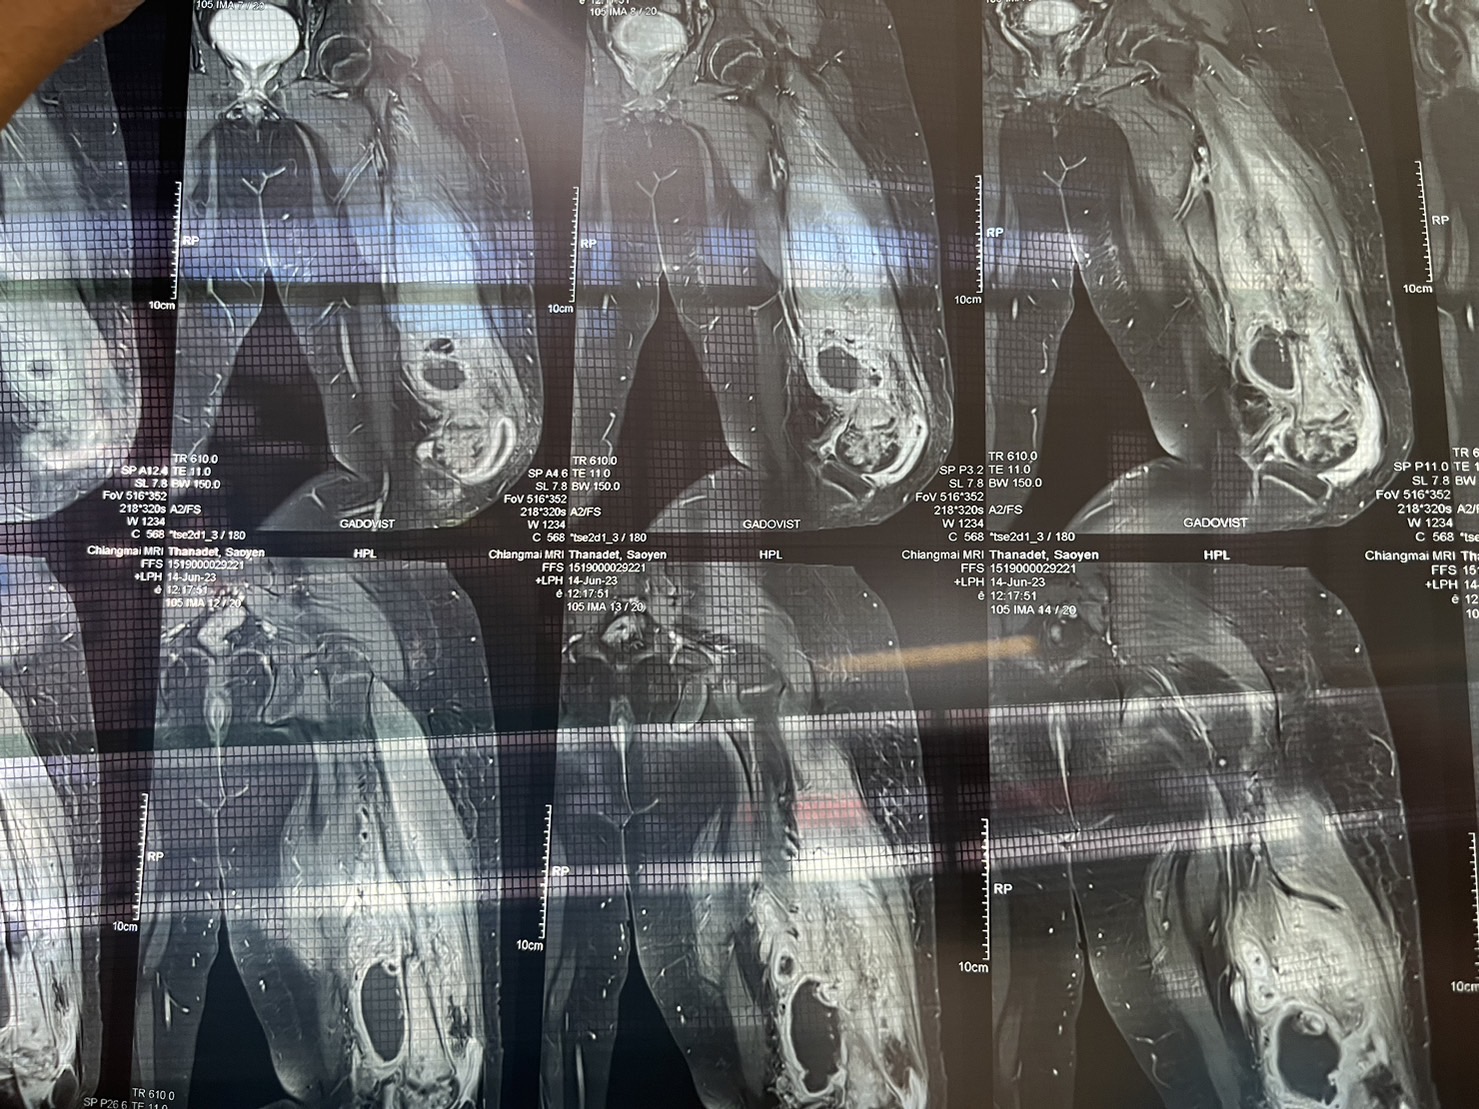

จนวันที่ 14มิ.ย.เด็กอาการหนักขึ้นรพ.ทุ่งหัวช้างส่งไปรักษาตัวที่รพ.ลำพูนและไปทำเอ็มอาร์ไอ(เอ็กซ์เรย์คอมพิวเตอร์)ที่เชียงใหม่และทราบผลเมื่อวานเด็กมีอาการหนักกระดูกอักเสบ มีหนองและฝีในในกระดูกจนกลายเป็นข่าวตอนนี้ทางโรงเรียนกำลังหารือเพื่อช่วยเหลือเด็กเช่นกันและจะเข้าไปเยี่ยมเด็กที่รพ.และที่ผ่านมาทางโรงเรียนและครูก็ไม่เคยละเลยเด็กคอยติดตามอาการเด็กมาโดยตลอดและสิ่งที่ต้องทำตอนนี้คือโพกัสในเรื่องการช่วยเด็กก่อน

จนล่าสุดผุ้ปกครองมาขอให้ไปส่งรพ.เพราะเด็กไม่เจ็บ ไม่ไข้ ไม่ปวดแต่ลุกไม่ได้จึงพาไปหมาหมอที่รพ.จนทราบว่าเด็กกระดูกแตกหักซึ่งตนเองก็ได้ถามหมอว่าการให้เด็กลุกนั่งจะทำให้เด็กกระดูกแตกหักได้หรือไม่ซึ่งหมอก็บอกว่าเป็นไปได้ยากเพราะเป็นกระดูกขาชิ้นใหญ่แข็งแรงมากต้องโดนกระแทกอย่างแรงเท่านั้นซึ่งผู้ปกครองก็ยืนยันว่าเด็กไม่เคยไปกระแทกหรือรถล้มแต่อย่างใด จนวันที่14มิ.ย.66พาไปเอ็มอาร์ไอที่เชียงใหม่และเมื่อวานนี้ทราบผลดังกล่าวและที่ผ่านมายืนยันว่าได้ติดตามและดูแลเด็กมาโดยตลอด